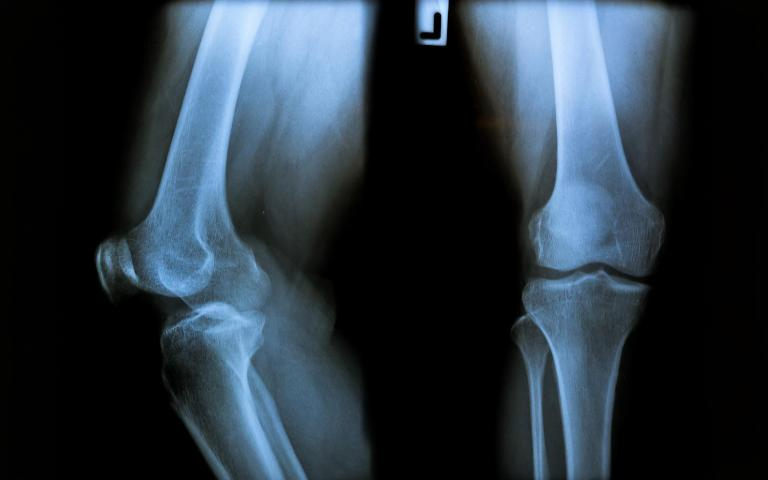

Knee replacement surgery is commonly advised for patients with advanced osteoarthritis, rheumatoid arthritis, post-traumatic arthritis, or severe joint deformity. Symptoms such as chronic pain, difficulty walking, reduced range of motion, and poor quality of life often indicate the need for surgical intervention. Each patient undergoes a detailed clinical assessment to ensure surgery is truly beneficial. As a trusted centre for knee replacement surgery in Islamabad, we prioritise accurate diagnosis and appropriate patient selection to achieve the best outcomes.